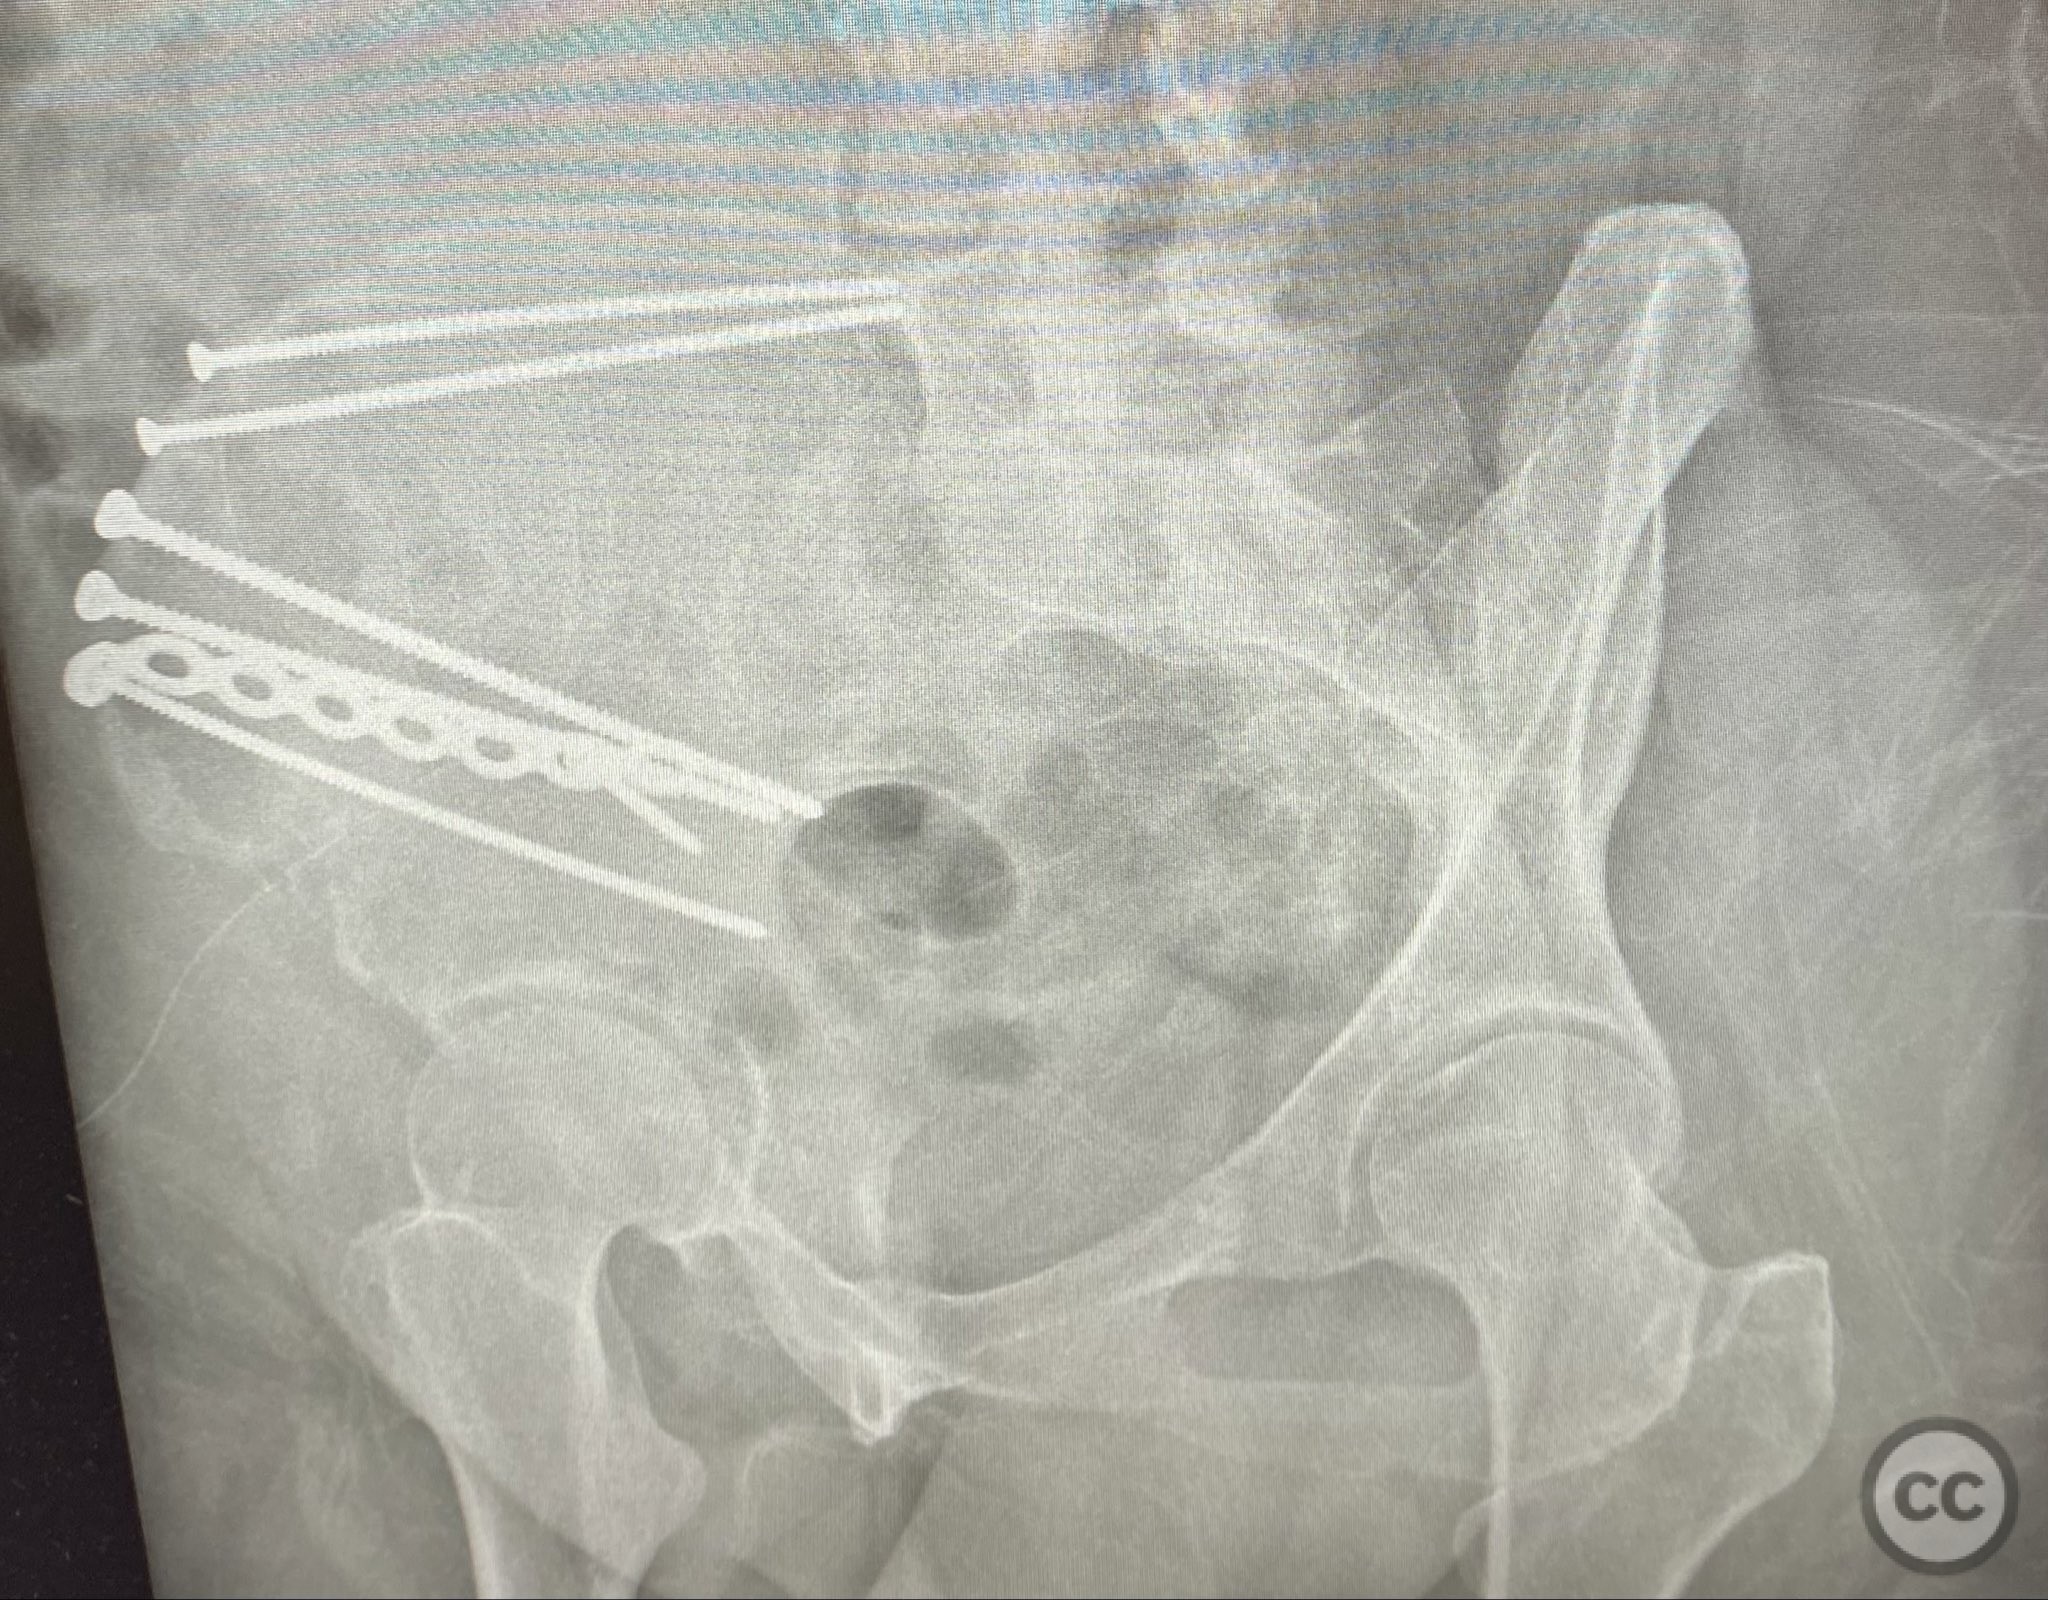

Operative remarks:

The comminuted fragments were mobilized and reduced using pointed reduction forceps and ball-spike pushers under direct vision. Lag screws were placed transversely between the inner and outer cortical tables of the ilium to achieve interfragmentary compression across major fracture lines. A pre-contoured reconstruction plate was then applied along the crest and tensioned to supplement the lag screws, providing additional stability across zones of comminution. The expanded exposure facilitated thorough cleaning of hematoma and debris, precise reduction, and secure clamp placement during fixation.

Orthopaedic implants used:   3.5mm cortical lag screws; pre-contoured 3.5mm reconstruction plate